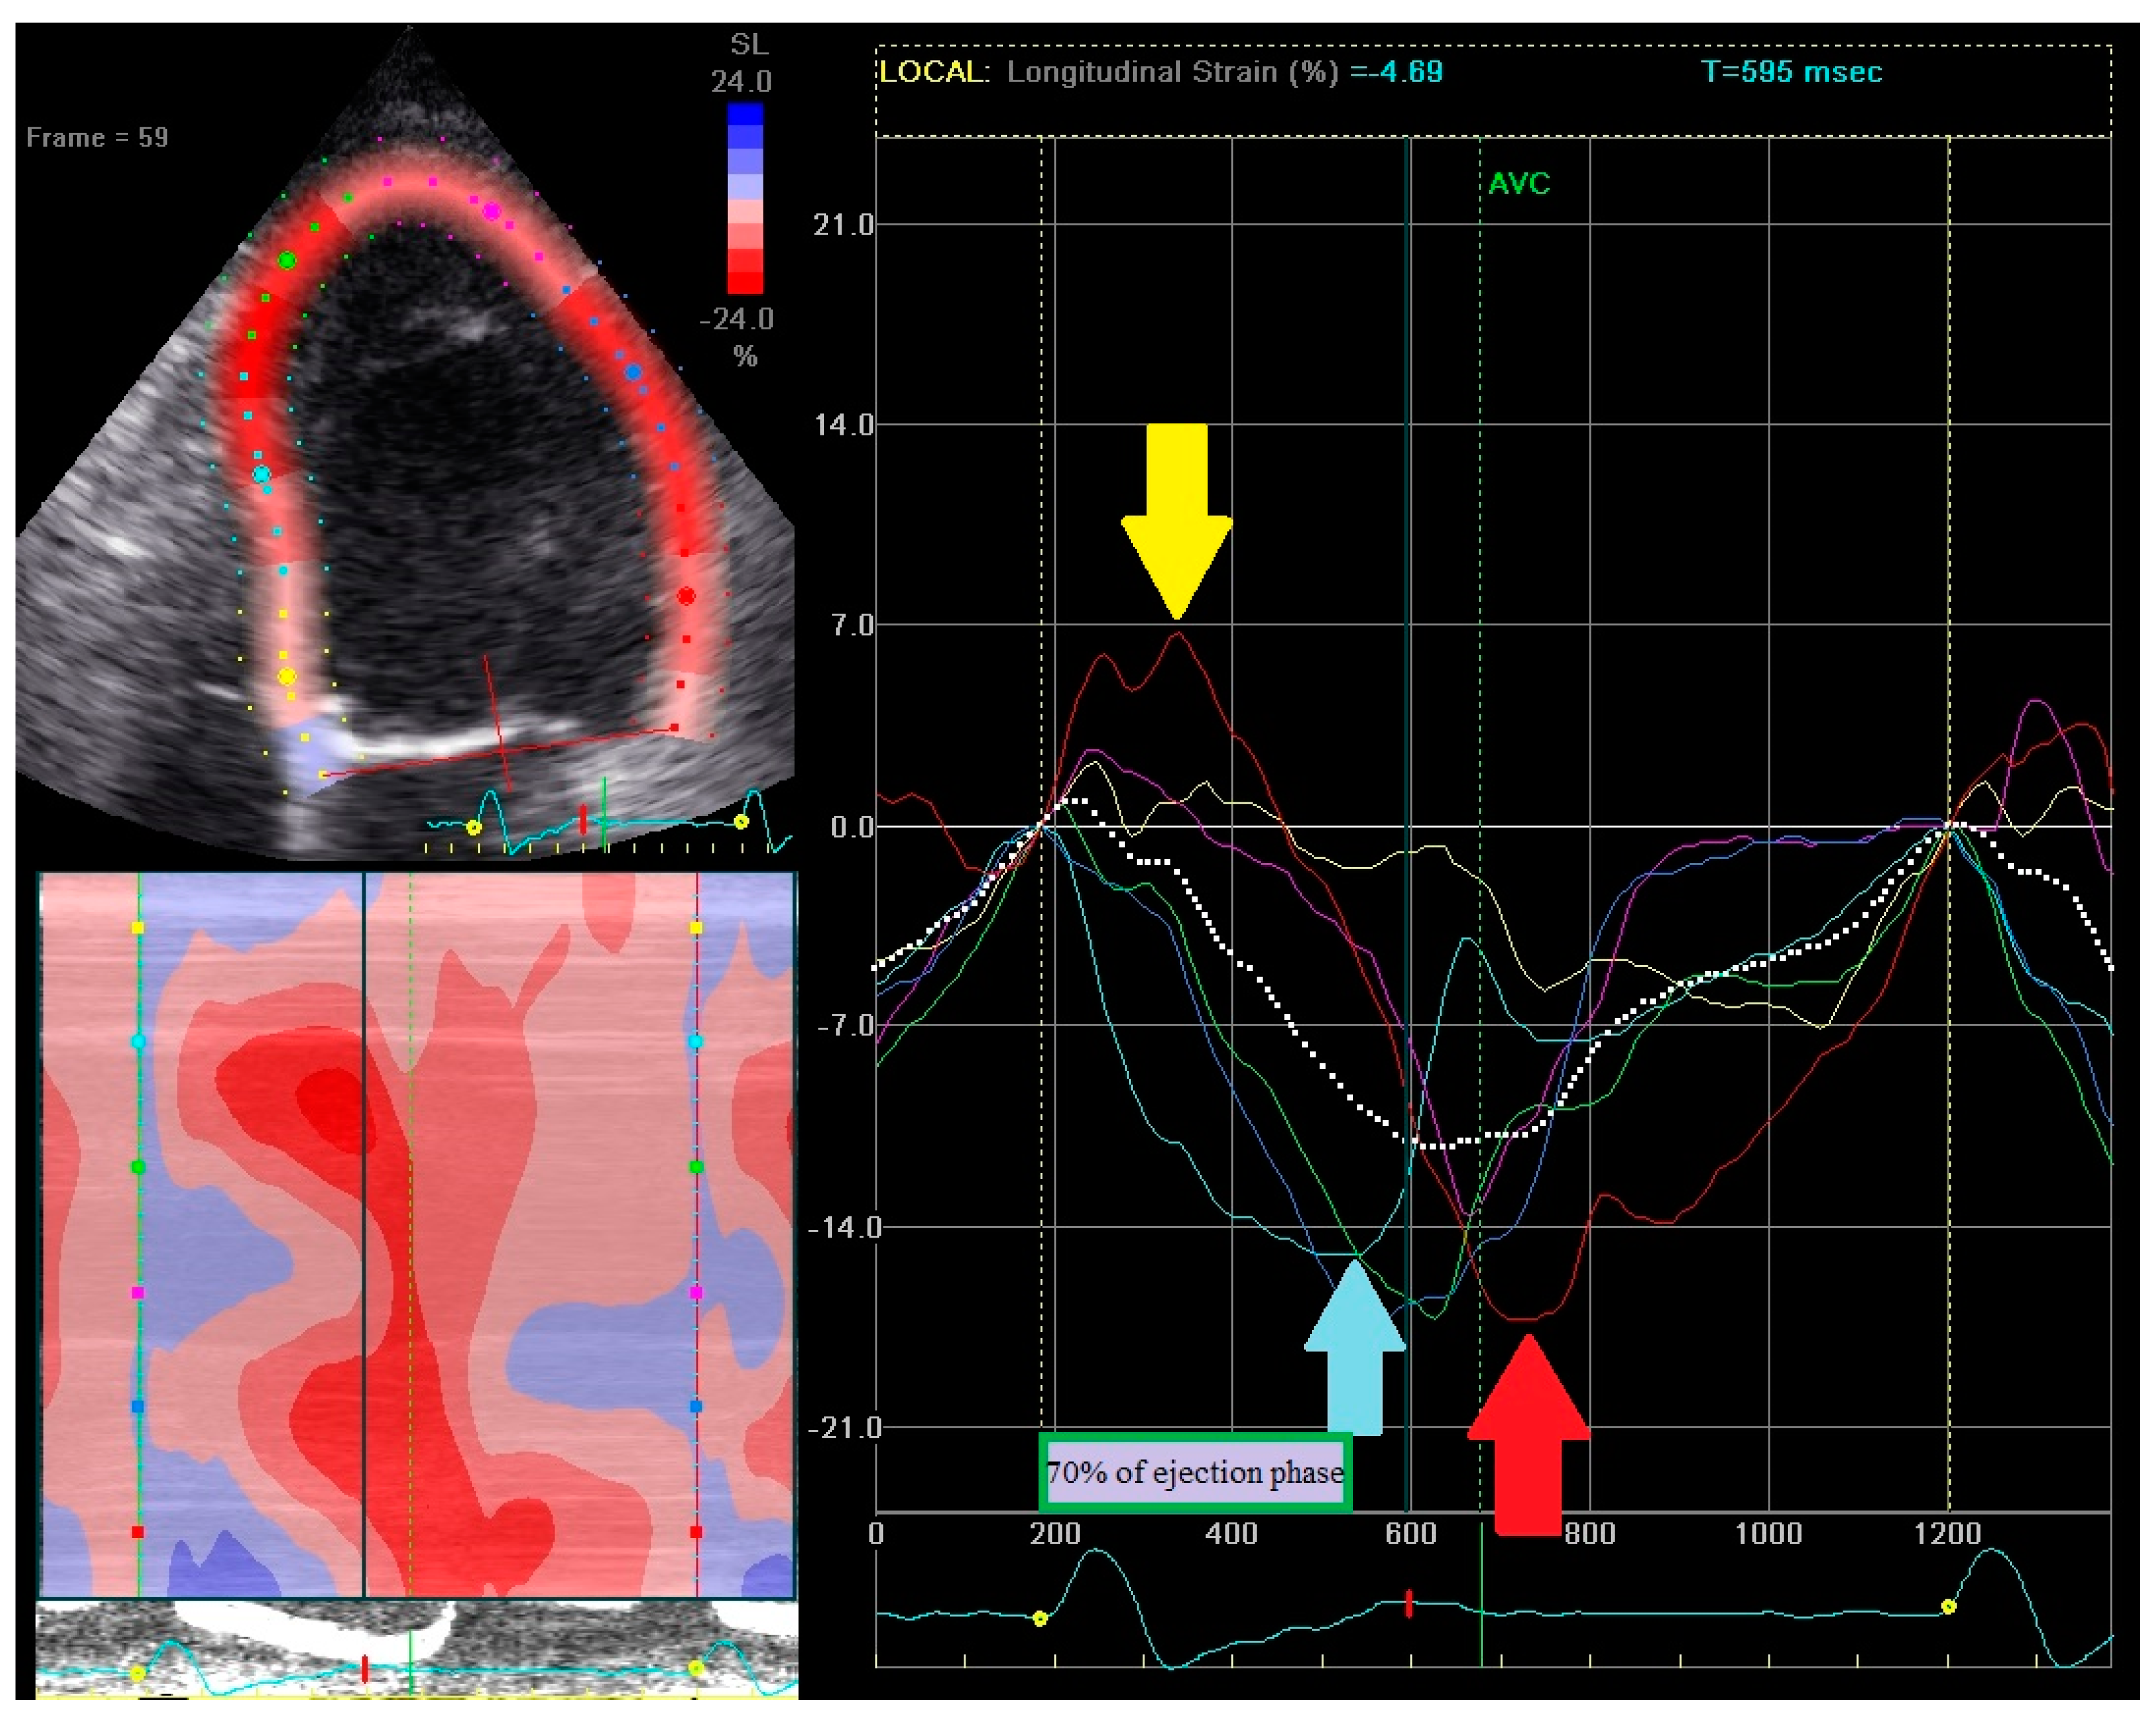

- (1)

- Early contraction of at least one basal or midventricular segment in septal or anteroseptal wall and early stretching in at least one basal or midventricular segment in the opposing wall,

- (2)

- the early peak contraction does not exceed 70% of the ejection phase,

- (3)

- the early stretching wall shows a peak contraction after aortic valve closure.